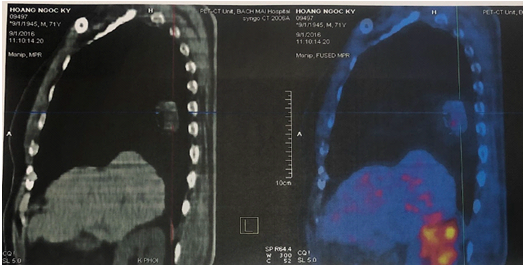

Bệnh nhân được chụp PET/CT sau 6 tháng để đánh giá hiệu quả điều trị, cho thấy khối mờ thùy dưới phổi phải dạng hang kích thước 31x29mm, bờ tua gai, phần đặc tăng hấp thu FDG, max SUV = 2,85. Không phát hiện hạch tăng chuyển hóa FDG khu trú, bất thường ở trung thất và rốn phổi hai bên. Không phát hiện tổn thương hấp thu FDG bất thường ở các vị trí khác.

Hình 5. Hình ảnh PET/CT cho thấy sự đáp ứng của bệnh sau 6 tháng điều trị: khối u thu nhỏ kích thước, tổn thương nhu mô não không tăng hấp thu F-18 FDG.

Như vậy, bệnh đáp ứng một phần, tổn thương não và hạch trung thất biến mất, kích thước khối u thu nhỏ. Bệnh nhân được tiếp tục duy trì phác đồ điều trị.